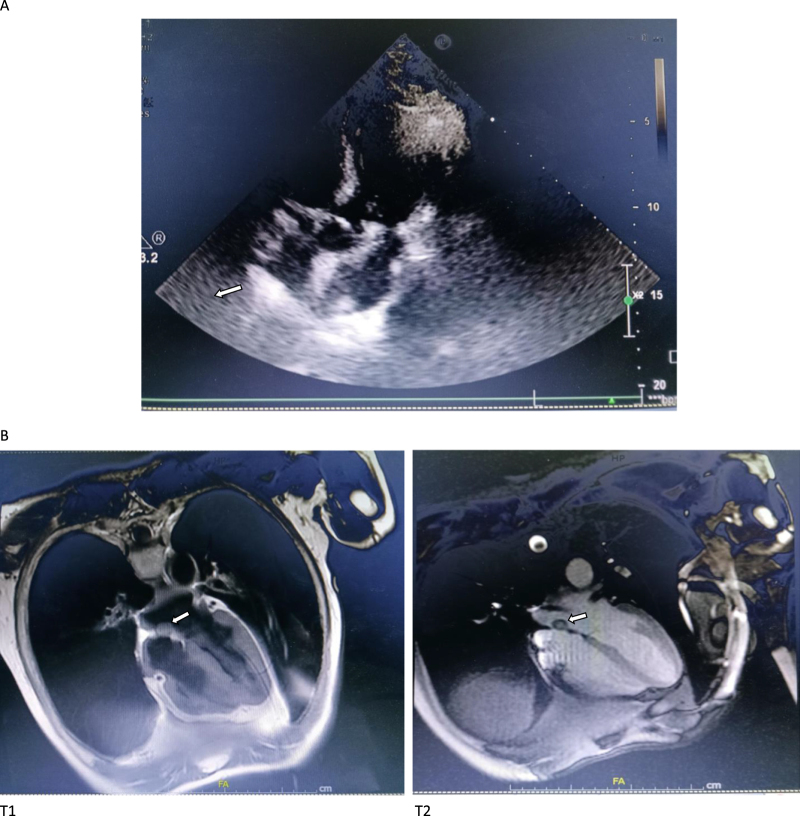

Case presentation: A 65-year old male patient with intermittent chest tightness and shortness of breath for 10 years was admitted for further work-up. On admission, the comprehensive metabolic panel (CMP) revealed a normal liver, kidney and coagulant function, and the BNP, troponin and CK-MB were within the normal limits. ECG showed a sinus rhythm. Cardiac catheterization revealed a three-vessel disease of CAD. Incidentally, echocardiography and MRI found a mobile mass, highly suspicious of cardiac myxomas on the imaging, at the left atrium. A coronary artery bypass grafting (CABG) combining with a right-atrium approach resection of the lesion were devised and concomitantly performed. No surgical complications and major cardiac adverse events occurred post-procedure. After anti-infection and supportive care, the patient recovered uneventfully. Follow-up at 6 months revealed no discomfort of the patient.